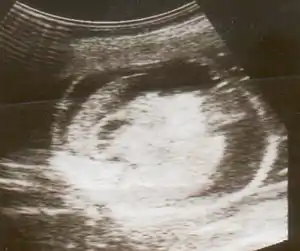

| An ultrasound showing a fetus with hydrops fetalis | |

Hydrops fetalis can be diagnosed and monitored by ultrasound scans. An official diagnosis is made by identifying excess serous fluid in at least one space (ascites, pleural effusion, of pericardial effusion) accompanied by skin edema (greater than 5 mm thick). A diagnosis can also be made by identifying excess serous fluid in two potential spaces without accompanying edema. Prenatal ultrasound scanning enables early recognition of hydrops fetalis and has been enhanced with the introduction of MCA Doppler.[5]